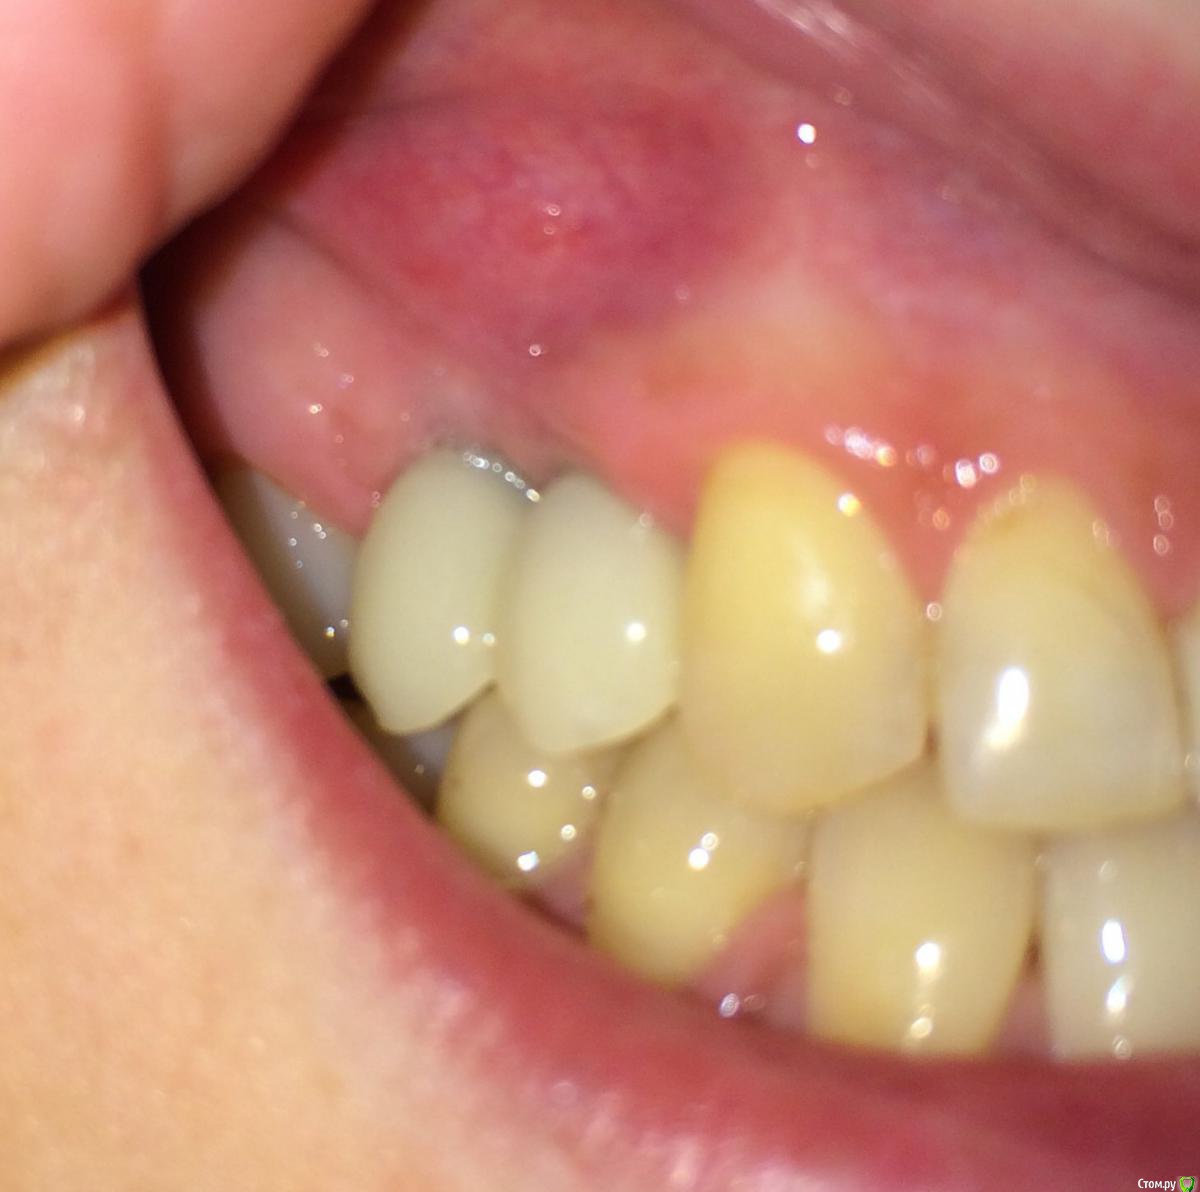

Nadiakroha Опубликовано 14 февраля, 2015 Поделиться Опубликовано 14 февраля, 2015 Здравствуйте, уважаемые специалисты! Месяц назад мне сделали наращивание десны над зубом 1,5, для более эстетичного формирования сосочка между зубами 1,4 и 1,5. Лоскут прижился, но меня беспокоит то, что проблема не решена, и врач говорит, что надо ждать до года результата, а после, возможно, и наращивать снова. Вопрос такой: грамотно ли была сделана операция? Поможет ли наращивание в формировании сосочка в данном случае? Ссылка на комментарий

Nadiakroha Опубликовано 14 февраля, 2015 Автор Поделиться Опубликовано 14 февраля, 2015 К сожалению фото до операции у меня нет, могу приложить только это же фото с другого ракурса.. Не слишком ли высоко десна наращена?На вторую часть вопроса прикрепляю снимок. Спасибо! Ссылка на комментарий

SDC Опубликовано 14 февраля, 2015 Поделиться Опубликовано 14 февраля, 2015 Не слишком ли высоко десна наращена? Что Вы имеете ввиду под высоко? Выбухание слизистой в преддверии? Там пластика не проводится и не нужна.В Вашем случае необходимо увеличивать объем мягких тканей в области шеек коронок. И помочь в этом может только одна донорская зона - бугор в.ч. - слишком велика горизонтальная и вертикальная атрофия альвеолярного отростка, где установлены имплантаты.С учетом положения платформ имплантатов, формы временных коронок, атрофии кости мне кажется, что потенциала для роста сосочка недостаточно. Ссылка на комментарий

Nadiakroha Опубликовано 14 февраля, 2015 Автор Поделиться Опубликовано 14 февраля, 2015 выкладываю фото, обвела пунктиром место наращенной десны. Извините, что столько времени у Вас отнимаю! Ссылка на комментарий

Nadiakroha Опубликовано 14 февраля, 2015 Автор Поделиться Опубликовано 14 февраля, 2015 (изменено) выкладываю фото, обвела пунктиром место наращенной десны. Извините, что столько времени у Вас отнимаю!Временные коронки стояли до операции по наращиванию, после заживления, через 10-12 дней поставили те же коронки, немного их подкорректировав, то есть сделали более естественную форму.. Вот фото коронок, до наращивания. Изменено 14 февраля, 2015 пользователем Nadiakroha Ссылка на комментарий

SDC Опубликовано 14 февраля, 2015 Поделиться Опубликовано 14 февраля, 2015 (изменено) выкладываю фото, обвела пунктиром место наращенной десны. Если так и есть, то это не тот регион, где необходимо увеличение объема.Трансплантированные ткани с бугра в.ч. действительно долго растут. И через год будет прирост, и через 2, но я сомневаюсь, что рост будет там, где нужно для эстетики. А зачем, в таком случае, снимали временные коронки? Насколько я вижу, трансплантация была на расстоянии от них? Изменено 14 февраля, 2015 пользователем SDC 1 Ссылка на комментарий